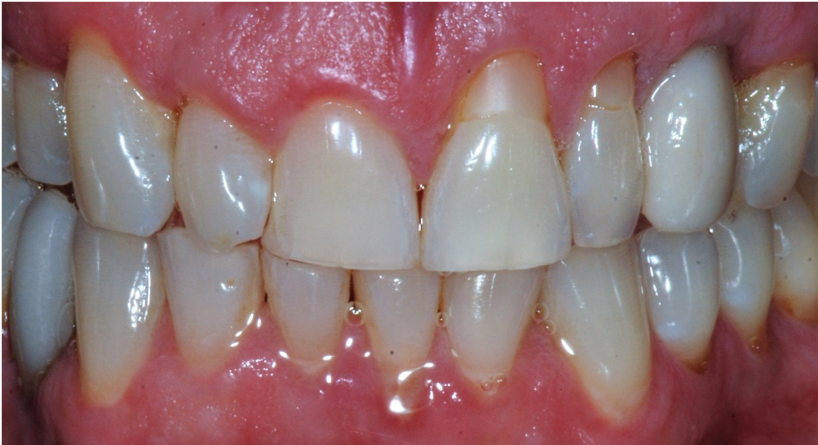

For this case, immediate loading was completed. Figure 16 shows the patient 2 weeks postoperatively. The tissue was healing well, and the patient decided to go through with bleaching his teeth. The results after 3 months of healing are shown in Figure 17. The shade was chosen by the patient. He then wanted to redo the rest of his teeth because of how successful the treatment was using digital dentistry.

Fig 16. Image taken 2 weeks postoperatively.

Figure 16

Fig 17. Image taken 3 months postoperatively.

Figure 17